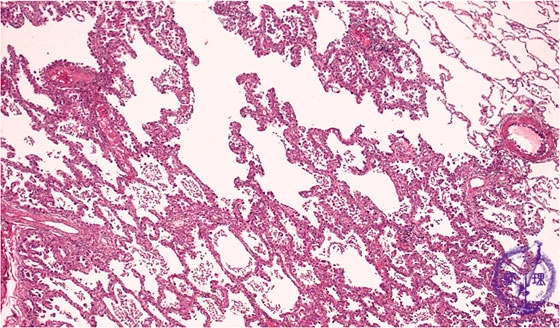

非小細胞肺癌(腺癌)ミクロ像(HE弱拡大)

ミクロ像(HE弱拡大):肺原発の腺癌では初期には既存の肺胞上皮を置換しながら増殖することが多く、細気管支肺胞上皮癌の形態を呈する。